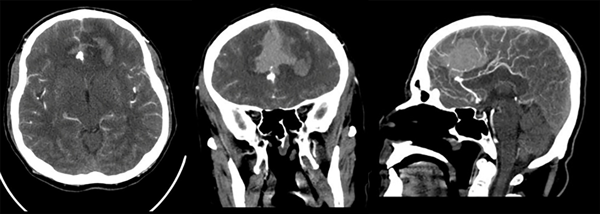

Paciente masculino de 47 años sin antecedentes patológicos de importancia, refiere inicio de enfermedad actual con cefalea súbita, severa, holocraneana, irradiada a región occipitocervical con vómitos en proyectil, desorientación, midriasis e incontinencia urinaria; es remitido a nuestra institución a los 16 días desde el inicio de los síntomas. Al ingreso se observa meningismo, trastornos en el nivel de conciencia e hipertensión arterial. En la tomografía de cerebro (TC) se observa una hemorragia subaracnoidea con un hematoma frontal bilateral. Se realiza angiotomografía cerebral donde se evidencia aneurisma sacular mediano trilobulado de ACAa (Figuras 1 y 2). Al examen físico de ingreso: bradipsíquico, bradilálico, somnoliento, desorientado, GCS 12/15 (respuesta ocular: 3, respuesta verbal: 3, respuesta motora: 6), pupilas isocóricas normorreactivas, sin focalidad de nervios craneales, vías largas: paraparesia 4/5 puntos (Daniels), rigidez de nuca leve y signo de Kernig. Se indica nimodipina 60 mg vía oral, medidas antiedema cerebral. Durante los días 2 y 24 de hospitalización se mantiene con clínica WFNS I, excepto el día 11 de hospitalización, donde se presenta deterioro neurológico por desorientación a WFNS II con evidencia de hiponatremia moderada (129 mEq/L). Se solicita tomografía cerebral simple control en la que se descarta resangrado e hidrocefalia, se indica corrección de sodio plasmático con mejoría evidente del estado neurológico a WFNS I. Se plantea intervención quirúrgica a las tres semanas del ingreso.

Figura 1. Angiotomografía cerebral. En cortes axial, coronal y sagital contrastados, se evidencia dilatación de aspecto sacular en fisura interhemisférica compatible con aneurisma de ACAa; hemorragia subaracnoidea en cisternas de la base y espacio subaracnoideo de la convexidad, hematoma intraparenquimatoso heterogéneo e irregular bifrontal.